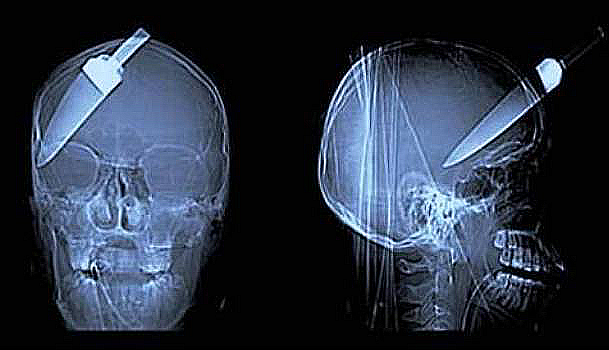

A large kidney stone

Yep, this white blob is actually a kidney stone that was removed from a man in Hungary. It weighted 2.5 pouds and measured 7 inches across.